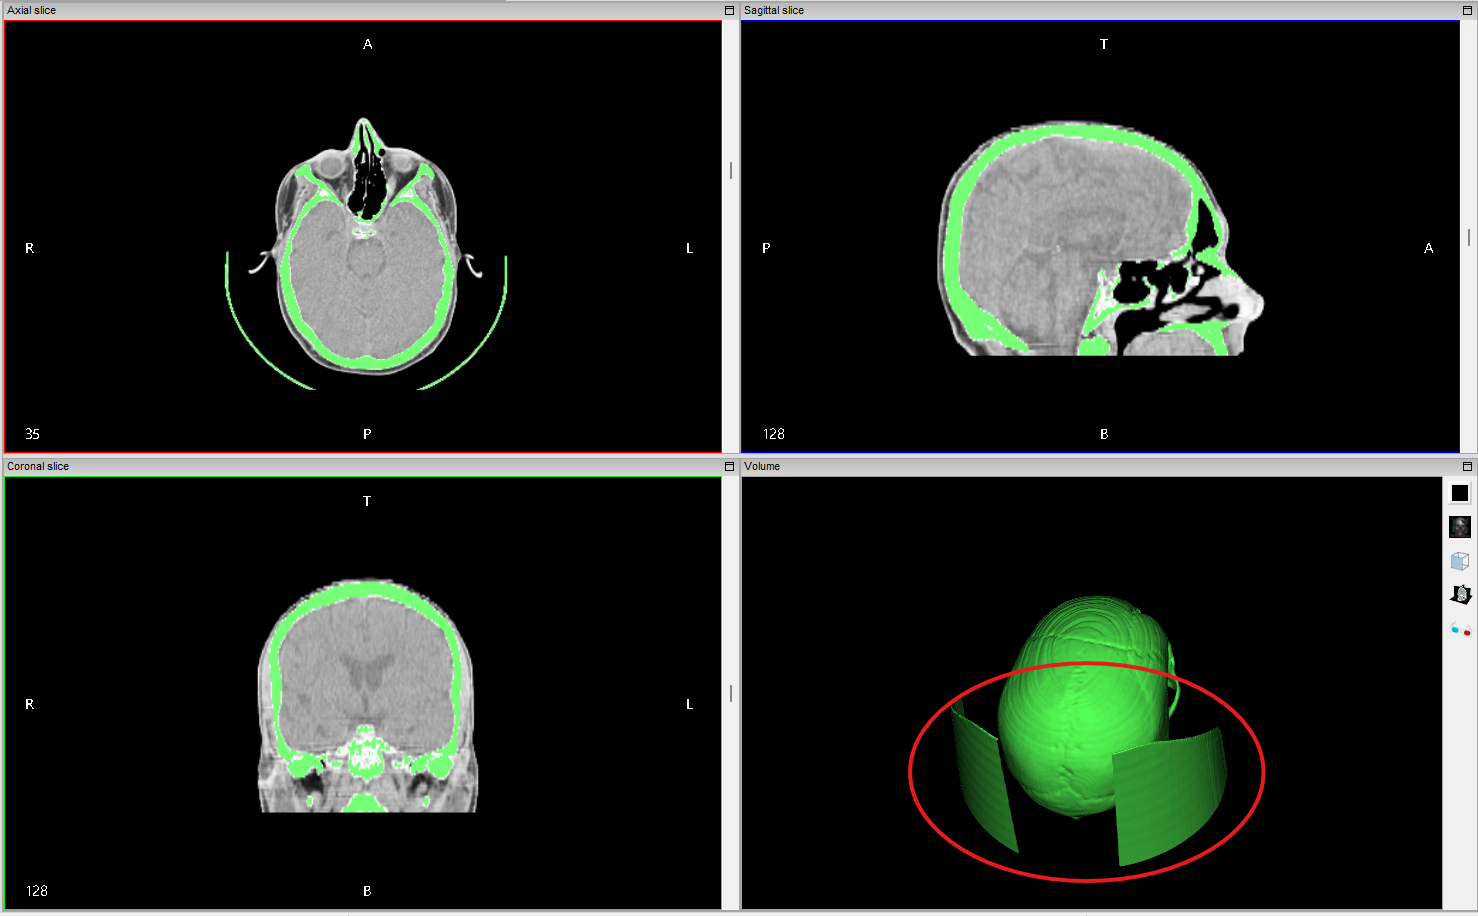

However, these tools are limited to 2D slices, which can be tedious and time-consuming. The project goal was to implement 3D mask edition tools to allow users to edit masks directly in the 3D view, making the process more intuitive and efficient. A typical use case is removing unwanted structures with similar intensity values as the target structure (see Figure 3).

- Interactive 3D Polygon Selection: Users can draw polygons directly on the 3D volume renderer to define regions for mask editing (keep/exclude inside polygon). The polygons are drawn in the screen space and projected into the 3D volume based on the current camera view.

- Real-Time Visualization: The current implementation provides immediate visual feedback of the masked volume as the polygons are modified and ajusted.